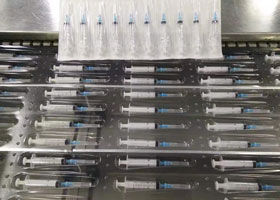

Vida is a high-tech manufacturing company committed to R&D, production

and marketing of medicaldisposable products and durable medical equipment

with main business covering medical protection, rehabilitation nursing,

physical therapy, disposable examination, operation products, and medical

consumables etc. Our company has passed the certification of medical and